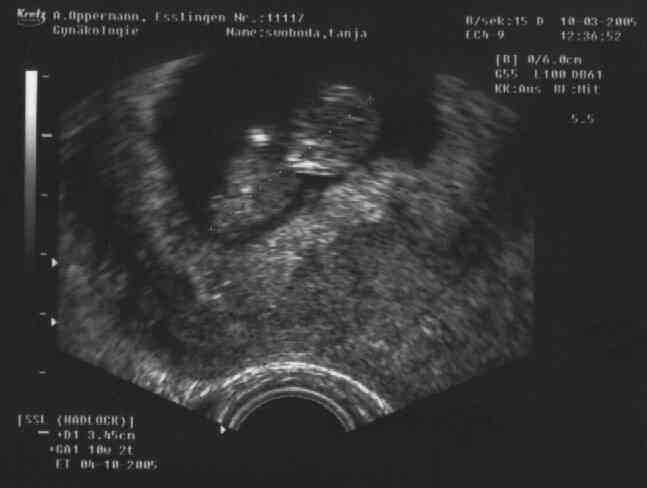

10. März 2005 12:36 (ca. 34,5mm)